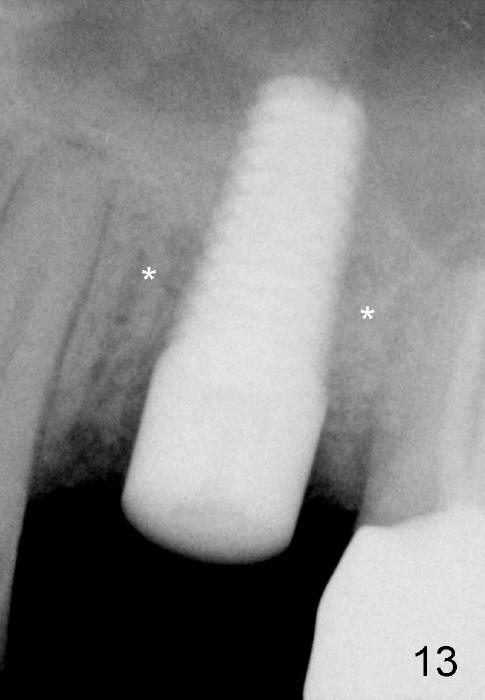

Four months postop, bone around the implant looks consolidated (Fig.13 *).